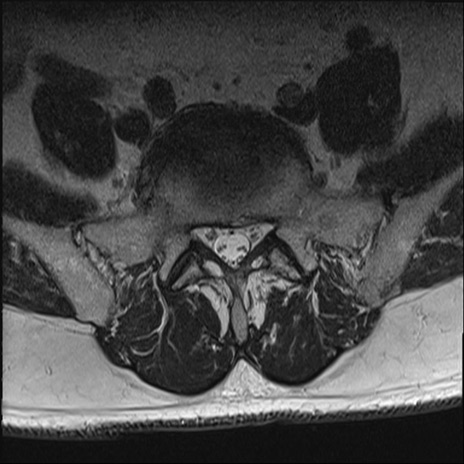

【整形】TIPS症例2 腰椎MRI T2WI(横断像)

【症例】70歳代男性

【主訴】左下肢痛

【現病歴】2週間前くらいから腰痛、左下肢痛あり。左臀部から大腿、下腿外側のしびれが常時ある。歩行とともに同部位の痛みあり。

【身体所見】Lasegue70-/60+、Bragard-/±、PTR ±/±、ATR -/-、IP 5/5、TA 5/4、TS 5/5、EHL 右第1足趾なし/3、FHL 5/5、hypersthesia(-)、足背動脈触知良好

異常所見と診断は?